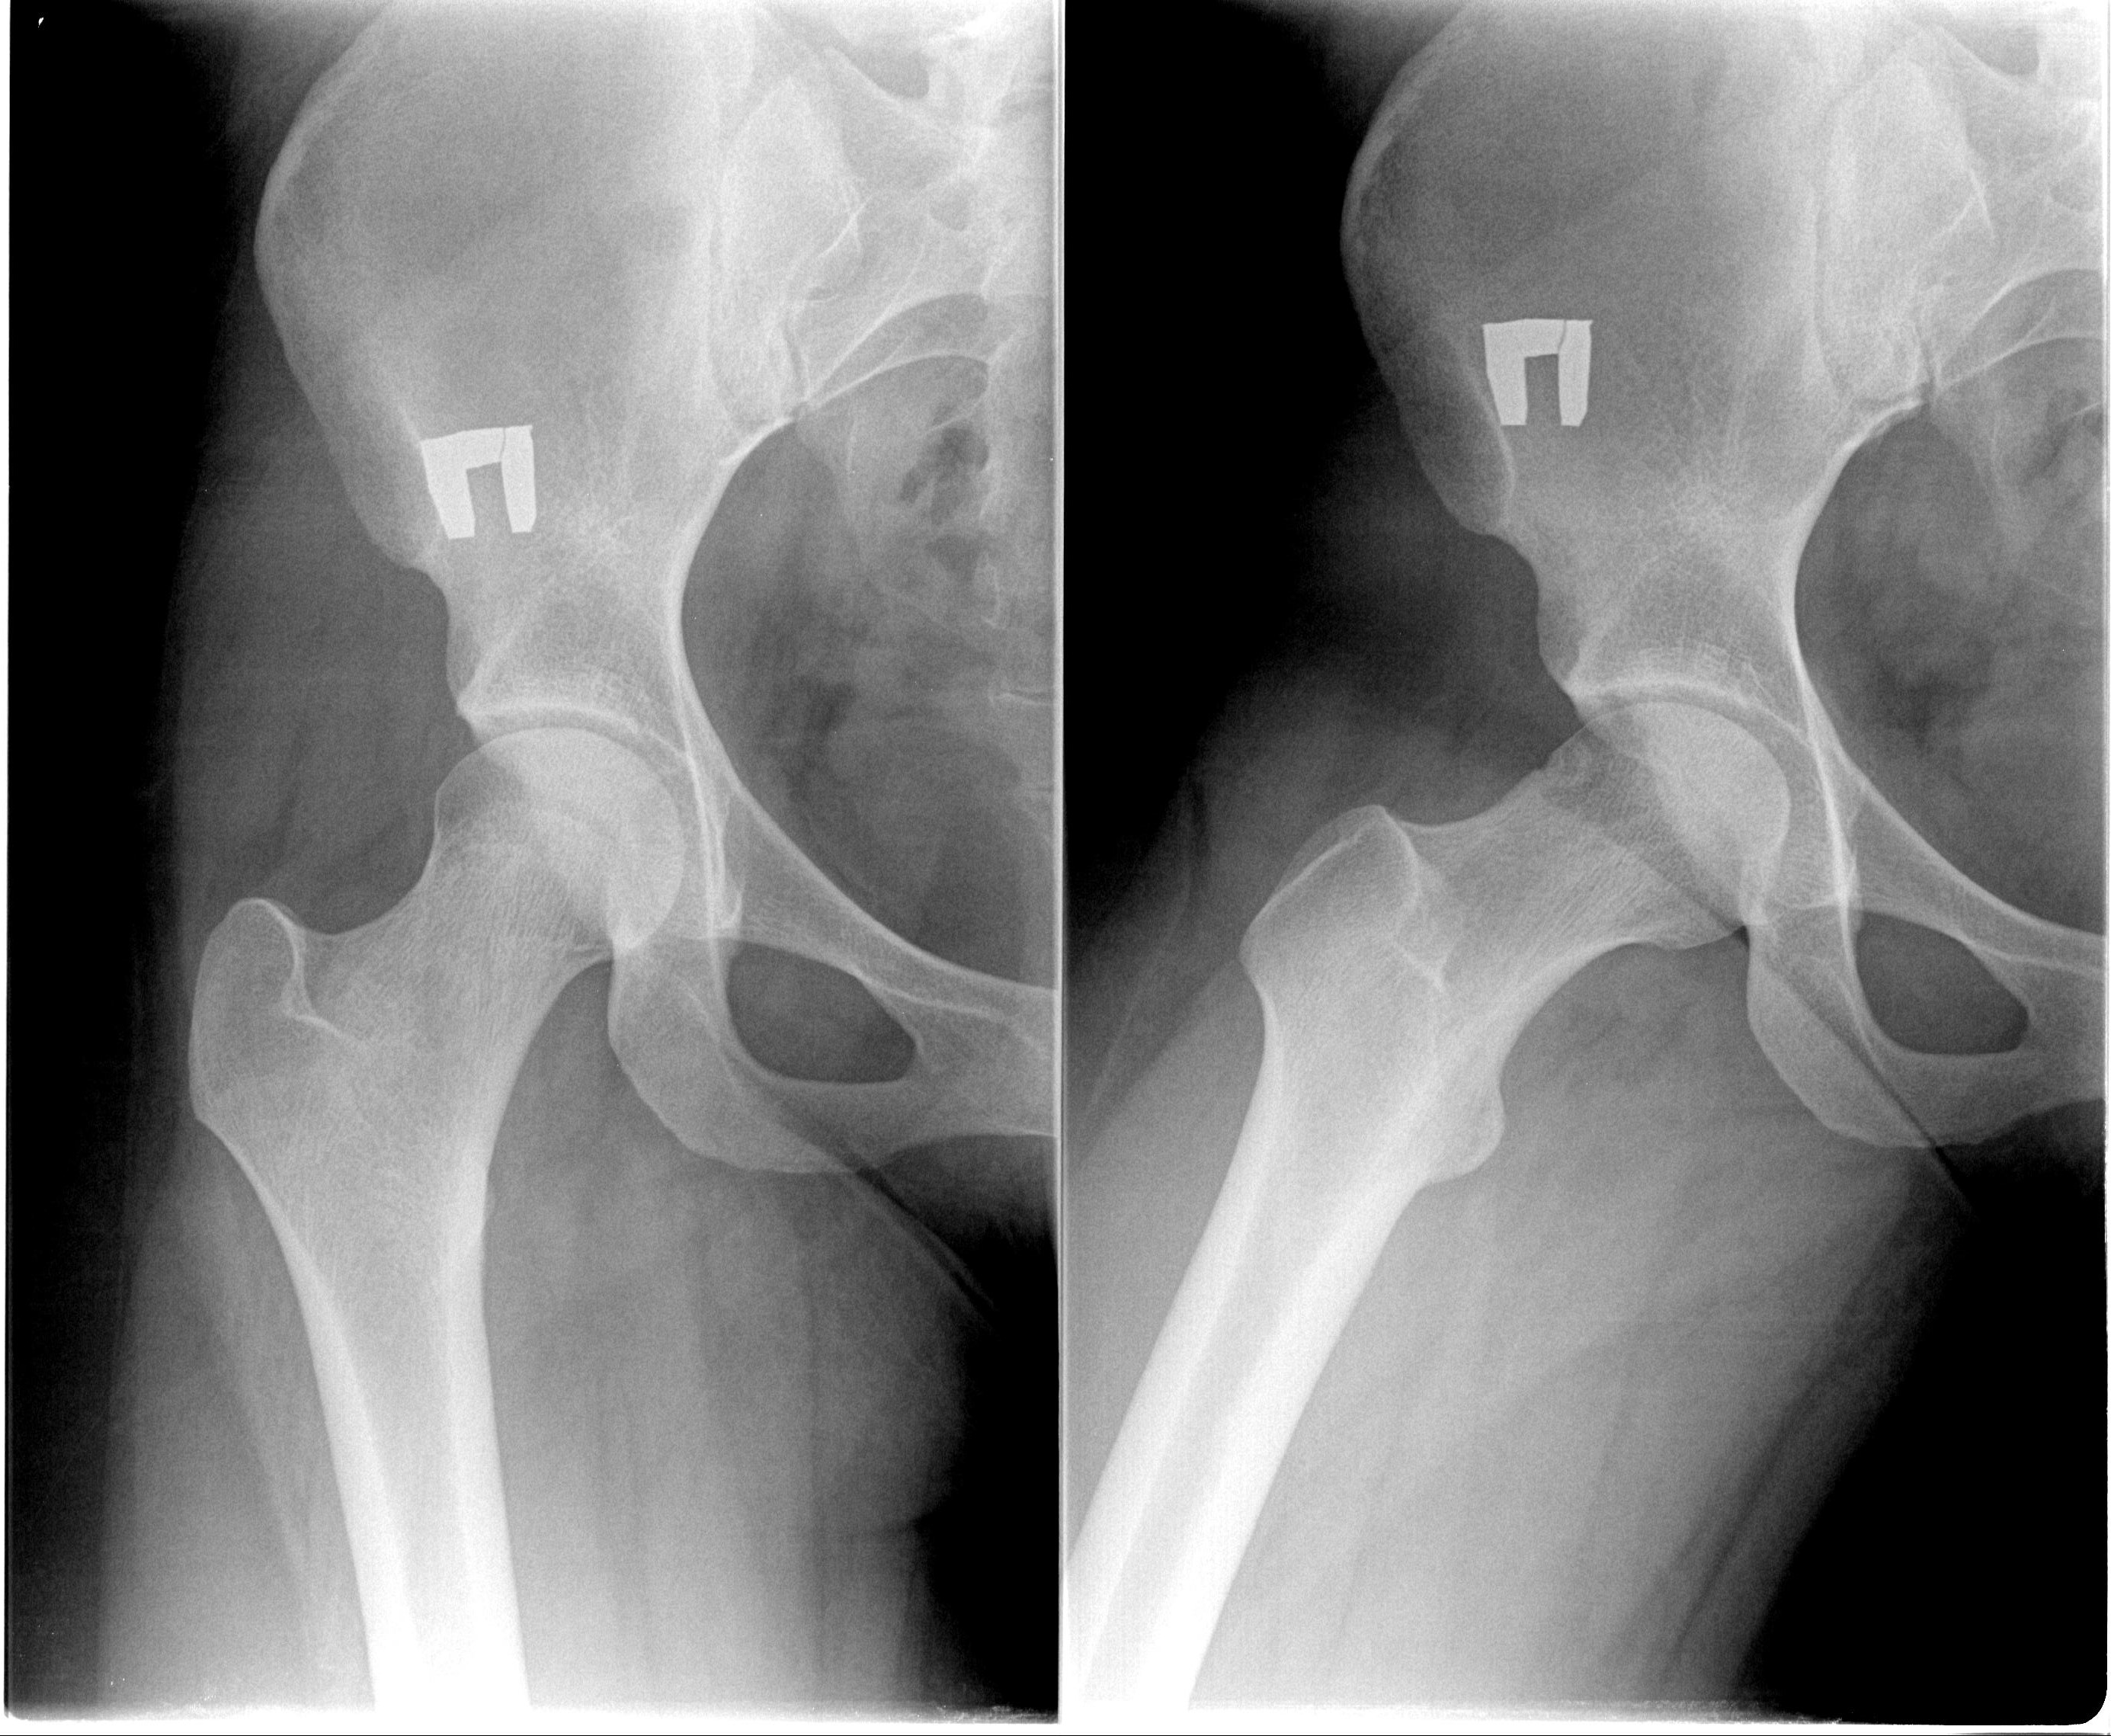

На рентгенограммах тазобедренный сустав сохраняет нормальную форму, суставная щель умеренно или неравномерно сужена с субхондральным склерозированием костных суставных поверхностей, непостоянными краевыми костными разрастаниями (I стадия).

Рентгенологически суставная щель может быть равномерно или неравномерно сужена, ацетабулярная суставная впадина уплощена, присутствуют явления субхондрального склероза, краевые костные разрастания. Конфигурация головки бедренной кости, как правило, не нарушена (II стадия).

В подавляющем большинстве случаев диагноз коксартроза ставится при рентгенографии, где видны изменения формы и структуры костей, составляющих тазобедренный сустав. Однако рентгенографически в ряде случаев затруднительно зафиксировать ранние проявления артроза, так как хрящевая ткань суставных поверхностей на рентгеновских снимках не отображается и мы можем судить о дегенеративном процессе, когда он достаточно выражен, вызывая изменения ширины просвета рентгеновской суставной щели.

КТ тазобедренного сустава проведено с 2002 года в 80, МРТ с 2011 года — в 22 случаях. Предпочтение следует отдать МРТ, так как при данном виде исследования можно четко визуализировать суставную капсулу и связки, идентифицировать даже поверхностные изменения хрящевого слоя, а также мелкие очаги субкортикального трабекулярного отека губчатого вещества костной ткани. КТ позволяет оценить минимальные изменения структуры и формы костной ткани, однако в общем объеме получаемой информации уступая МРТ в информативности. При углубленном обследовании для уточнения диагноза «коксартроз» и степени его выраженности можно рекомендовать проведение именно МРТ тазобедренных суставов.

На ранних стадиях диагностировать артроз можно только при проведении КТ или МРТ.